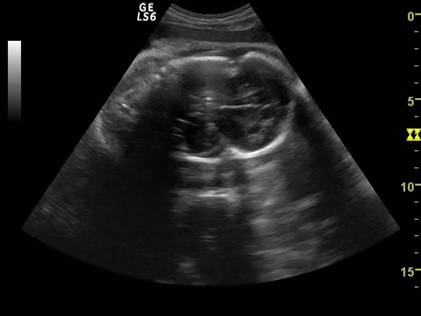

Fig. nr.238. Deformarea craniului la fat mort intrauterin

( aceeasi sarcina ca in figura precedenta )